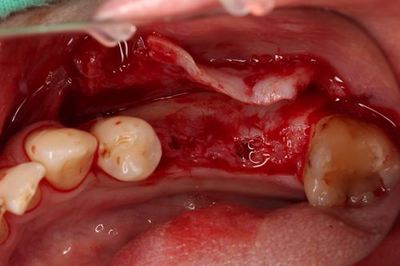

粘膜剥離前に安全な範囲で、ある程度のドリリングを終えました。

この時点で粘膜剥離します。

![]()